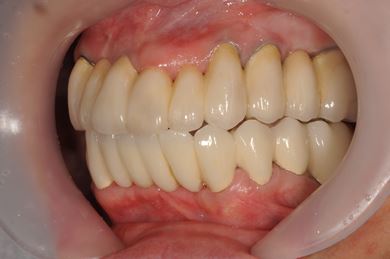

骨再生スピードインプラント治療+セラミック治療

| 性別/年齢 | 女性 / 43歳 | ||||||||||||||||||||||||||||||||

| 主訴 | 骨が薄いが、インプラント治療を希望。 | ||||||||||||||||||||||||||||||||

| 治療方針 | 抜歯と同時にインプラントを埋入し、治療期間を短縮する。ソケットリフトにて上顎洞を拳上し、インプラント治療を可能にする。 | ||||||||||||||||||||||||||||||||

| 治療内容 | インプラント9本(抜歯即日スピードインプラント、ソケットリフト、テンポラリーインプラント+仮歯)、メタルボンドセラミッククラウン18本、メタルボンドセラミックブリッジ6本(メタルボンド用土台6本)、遊離歯肉移植術 | ||||||||||||||||||||||||||||||||

| 総治療費 | 6,282,150円 | ||||||||||||||||||||||||||||||||

| 治療期間 | 1年8ヶ月 |